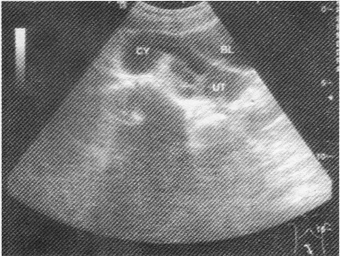

女性,26岁,下腹部疼痛数月。妇科检查右侧附件区增厚、增大,超声检查如图所示,最可能的诊断为

• A.右侧卵巢黄体囊肿

• B.右侧输尿管扩张

• C.右侧输卵管积液

• D.盆腔积液

• E.右侧卵巢畸胎瘤